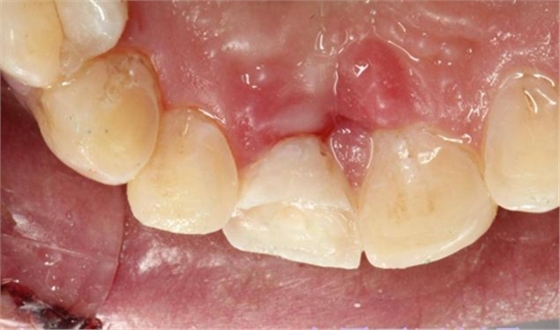

首先為了粘結(jié)斷端,選擇去除牙髓,行一次性根管治療后,首先處理舌側(cè)碎片,圖中可見(jiàn)舌側(cè)碎片裂至齦下,且牙齦有明顯撕裂,如果拔除折裂片,則難以修復(fù),或者選擇牙冠延長(zhǎng)或者選擇即刻種植,本人做了一種嘗試:粘結(jié)舌側(cè)碎片,首先對(duì)位碎片,發(fā)現(xiàn)對(duì)位后非常密合,如果采用全酸蝕粘結(jié)手段,則務(wù)必要掀開(kāi)碎片,則有可能導(dǎo)致出血污染粘結(jié)面,導(dǎo)致粘結(jié)失敗。于是小心謹(jǐn)慎輕微掀開(kāi)碎片,無(wú)滲血,用最小號(hào)毛刷蘸入自酸蝕粘結(jié)劑,然后直接復(fù)位碎片,并且壓緊,讓粘結(jié)劑能均勻擴(kuò)散至斷面深處,光固化。術(shù)畢檢查,碎片粘結(jié)完好。如下圖:

因周末處理該患者,無(wú)法領(lǐng)取纖維樁,于是將切斷的碎片復(fù)位后,從碎片舌側(cè)面制備一隧道直至根管口深處,(想法是注入流體樹(shù)脂形成一個(gè)樹(shù)脂樁加強(qiáng)固位),然后同上病例中所用方法,粘結(jié)固定斷端。如下圖: